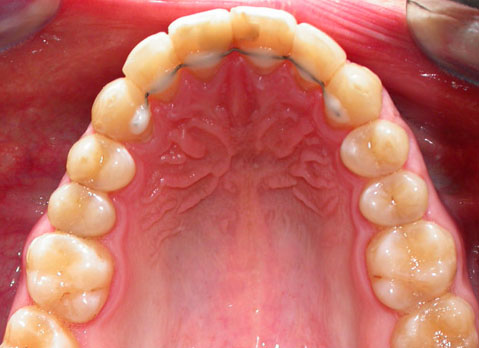

Лечение проводилось с апроксимальной сепарацией эмали зубов. Применялись керамические брекеты.

Результат получен спустя 18 месяцев после начала лечения